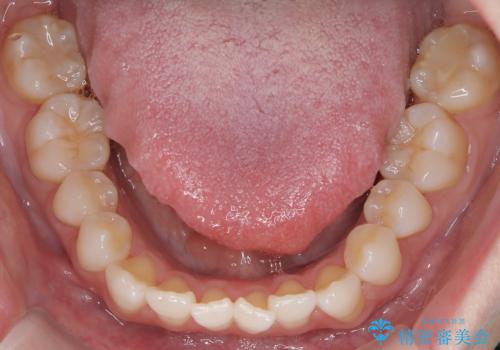

インビザラインモデレートによる前歯の叢生改善|IPR最小限で自然な歯並びへ

- 患者様は、**前歯の叢生(がたつき)**を気にされて来院されました。

できるだけ歯を削らずに、自然な歯並びを手に入れたいというご希望がありました。

診査の結果、中等度の叢生であったため、インビザラインモデレートでの対応が可能と判断しました。

歯へのダメージを抑えるため、IPR(歯間削合)は必要最小限にとどめる方針としました。

前歯の叢生は解消され、自然で調和の取れた歯並びが得られました。

「歯をほとんど削らずにきれいになった」と、患者様にもご満足いただけました。